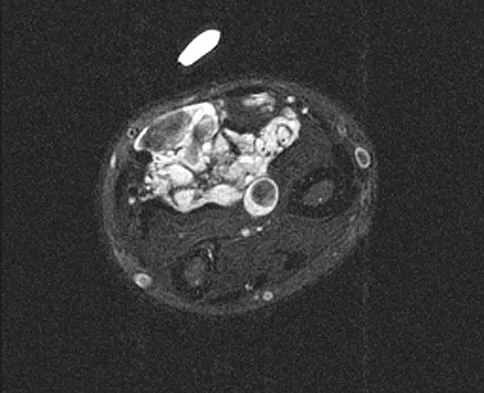

A 35-year-old woman states that she stepped on a piece of glass 6 months ago and reports numbness and shooting pain along the plantar lateral forefoot. She had previously received steroid injections in the 3 to 4 webspace. Examination reveals mild tenderness along the plantar fascia; no Tinel's sign is noted plantar medially and no Mulder's click is noted distally. An MRI scan is shown in Figure 7. What is the most likely cause of the numbness?

Explanation

The MRI scan reveals a laceration through the abductor hallucis musculature and lateral plantar nerve, producing numbness along its distribution. There is no evidence of a foreign body on the MRI scan. Baxter's nerve, or nerve to the abductor digiti quinti muscle, is the first branch off the lateral plantar nerve and impingement of this nerve typically produces a Tinel's sign along the nerve branch deep to the abductor hallucis muscle. Interdigital neuroma would be suggested by the presence of a Mulder's click. A digital nerve laceration would exhibit isolated numbness more distally. Baxter DE, Pfeffer GB: Treatment of chronic heel pain by surgical release of the first branch of the lateral plantar nerve. Clin Orthop Relat Res 1992;279:229-236.